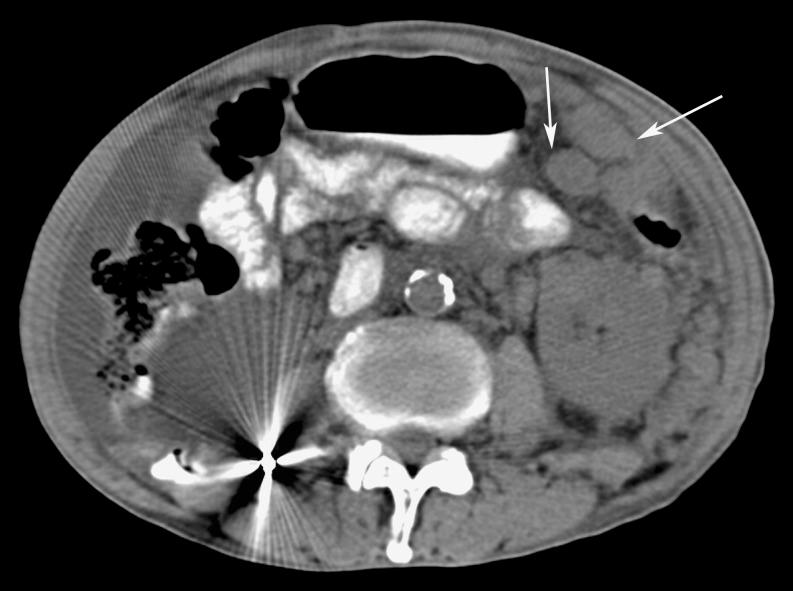

Omental cakes typically are associated with ovarian carcinoma, as this is the most common malignant aetiology. Nonetheless, numerous other neoplasms, as well as infectious and benign processes, can produce omental cakes. METHODS: A broader knowledge of the various causes of omental cakes is valuable diagnostically and to direct appropriate clinical management. RESULTS: We present a spectrum of both common and unusual aetiologies that demonstrate the variable computed tomographic appearances of omental cakes. CONCLUSION: The anatomy and embryology are discussed, as well as the importance of biopsy when the aetiology of omental cakes is uncertain.